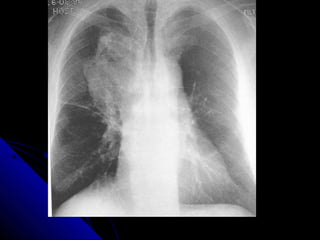

CCHHFF

CCaarrddiioommeeggaallllyy..

UUppppeerr lloobbee ddiivveerrssiioonn..

KKeerrlleeyy--BBlliinneess..

PPlleeuurraall eeffffuussiioonn..

BBaattwwiinngg eeddeemmaa..